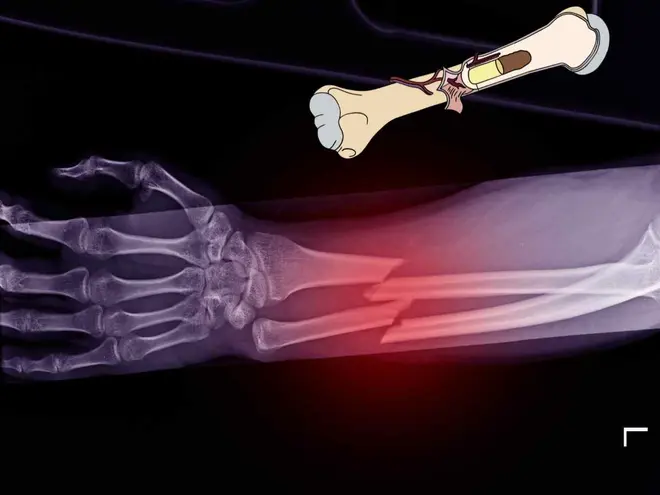

China.- Imagina poder unir en minutos los huesos fracturados con un pegamento. Podría ser posible con el biomaterial adhesivo que fabricaron los expertos del Hospital Sir Run Run Shaw de la Universidad de Zhejiang (ZJU) en China.

Este “pegamento para los huesos” promete una recuperación instantánea incluso en la presencia de sangre. Es la respuesta a uno de los retos clínicos más difíciles: arreglar huesos rotos sin dejar cicatrices metálicas.

El “pegamento para reparar fracturas”, llamado Bone 02, es el primer material adhesivo para los huesos capaz de lograr una unión fuerte e instantánea en el torrente sanguíneo humano. Su existencia se debe a una curiosa inspiración milenaria: la naturaleza.

Bone 02 aborda la necesidad de una fijación precisa y rápida, especialmente crucial en el caso de la unión de pequeños fragmentos óseos.

- Unión rápida: Logra una adhesión instantánea y fuerte en tan solo 2 a 3 minutos, incluso en un ambiente fisiológico húmedo infiltrado por sangre.

- Gran resistencia: Los experimentos han confirmado que la fuerza máxima de tracción de la unión de Bone 02 puede superar los 180 kilogramos (kg), mostrando potencial para reemplazar los fijadores internos metálicos tradicionales.

- Cirugía mínimamente invasiva: Permite inyectar el material adhesivo a través de una incisión pequeña (por ejemplo, de 2 a 3 centímetros), logrando una fijación precisa de los fragmentos pequeños.

- El material es completamente biodegradable y se absorbe de forma natural a medida que el hueso sana (aproximadamente 6 meses), lo que elimina la necesidad de una segunda operación para remover el material.

- Bone 02 demostró seguridad y eficacia en más de 150 pacientes durante el primer estudio clínico multicéntrico, aleatorizado y controlado del mundo sobre fijación adhesiva para fracturas conminutas.